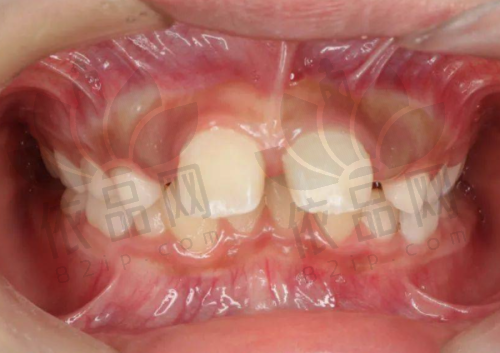

一家连锁口腔所属商圈为中山路,是连锁口腔医院。院内实行24小时电话预约制度,开设有晚班,患者可提前预约,无需等待直接就诊。院内还贴心为患者准备了免费的茶水、WIFI、儿童游乐区、VIP等候休息区等。它是国内连锁的品牌,在多个城市都有连锁店,除了乌鲁木齐天山区和水磨沟区有两家外,西安、咸阳、宝鸡等城市也有特别多家。其全称是一家连锁口腔中山路门诊部,审批机关是乌鲁木齐市天山区卫生健康委员会,登记号为6501020097,诊疗项目包括口腔科、牙体牙髓病、牙周病、口腔粘膜病、儿童口腔、口腔颌面外科、口腔修复、口腔正畸、口腔种植、口腔麻醉、口腔颌面医学影像、预防口腔,还有医学检验科的临床体液、血等。

一家有名口腔所属商圈是光明路,品牌在国内出名,有30多家连锁分院,在乌鲁木齐有两家,凭借品牌优势,特别受本地人认可。这里汇聚了一批口腔医生,配备了新型的口腔设备,如三维口腔CT、美国隐适美itero口扫仪等,能确保诊疗结果的正确性和可靠性。该门诊部创办于2013年,目前在天山区和新市区拥有两家地方分院,优势口腔治疗项目包括牙齿矫正、牙齿种植、牙齿修复、牙齿美白、儿童齿科等。